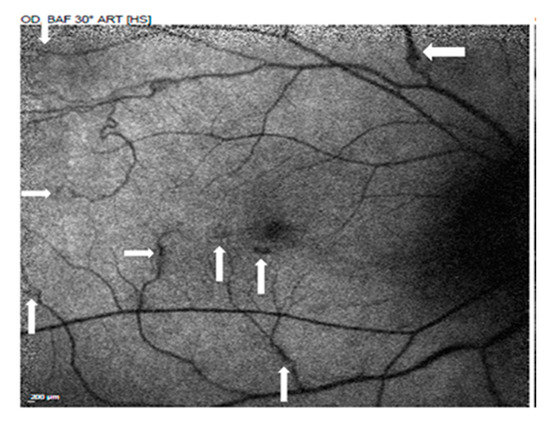

Use of Ultra-Widefield Fluorescein Angiography to Guide the Treatment to Idiopathic Retinal Vasculitis, Aneurysms, and Neuroretinitis—Case Report and Literature Review

2. Case Presentation